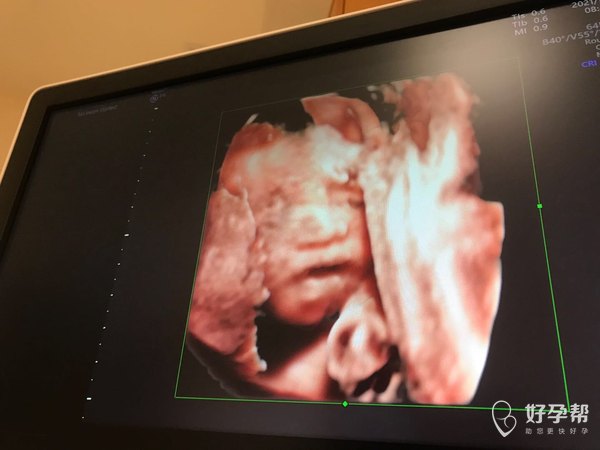

宝宝头上这是啥四维彩超医生说正常的

看四维彩超要动态看,这样定格的是瞬间,可能是别的部位一起拍下来了,那个地方是额头,没有什么的,异常超声医生肯定回会报的。